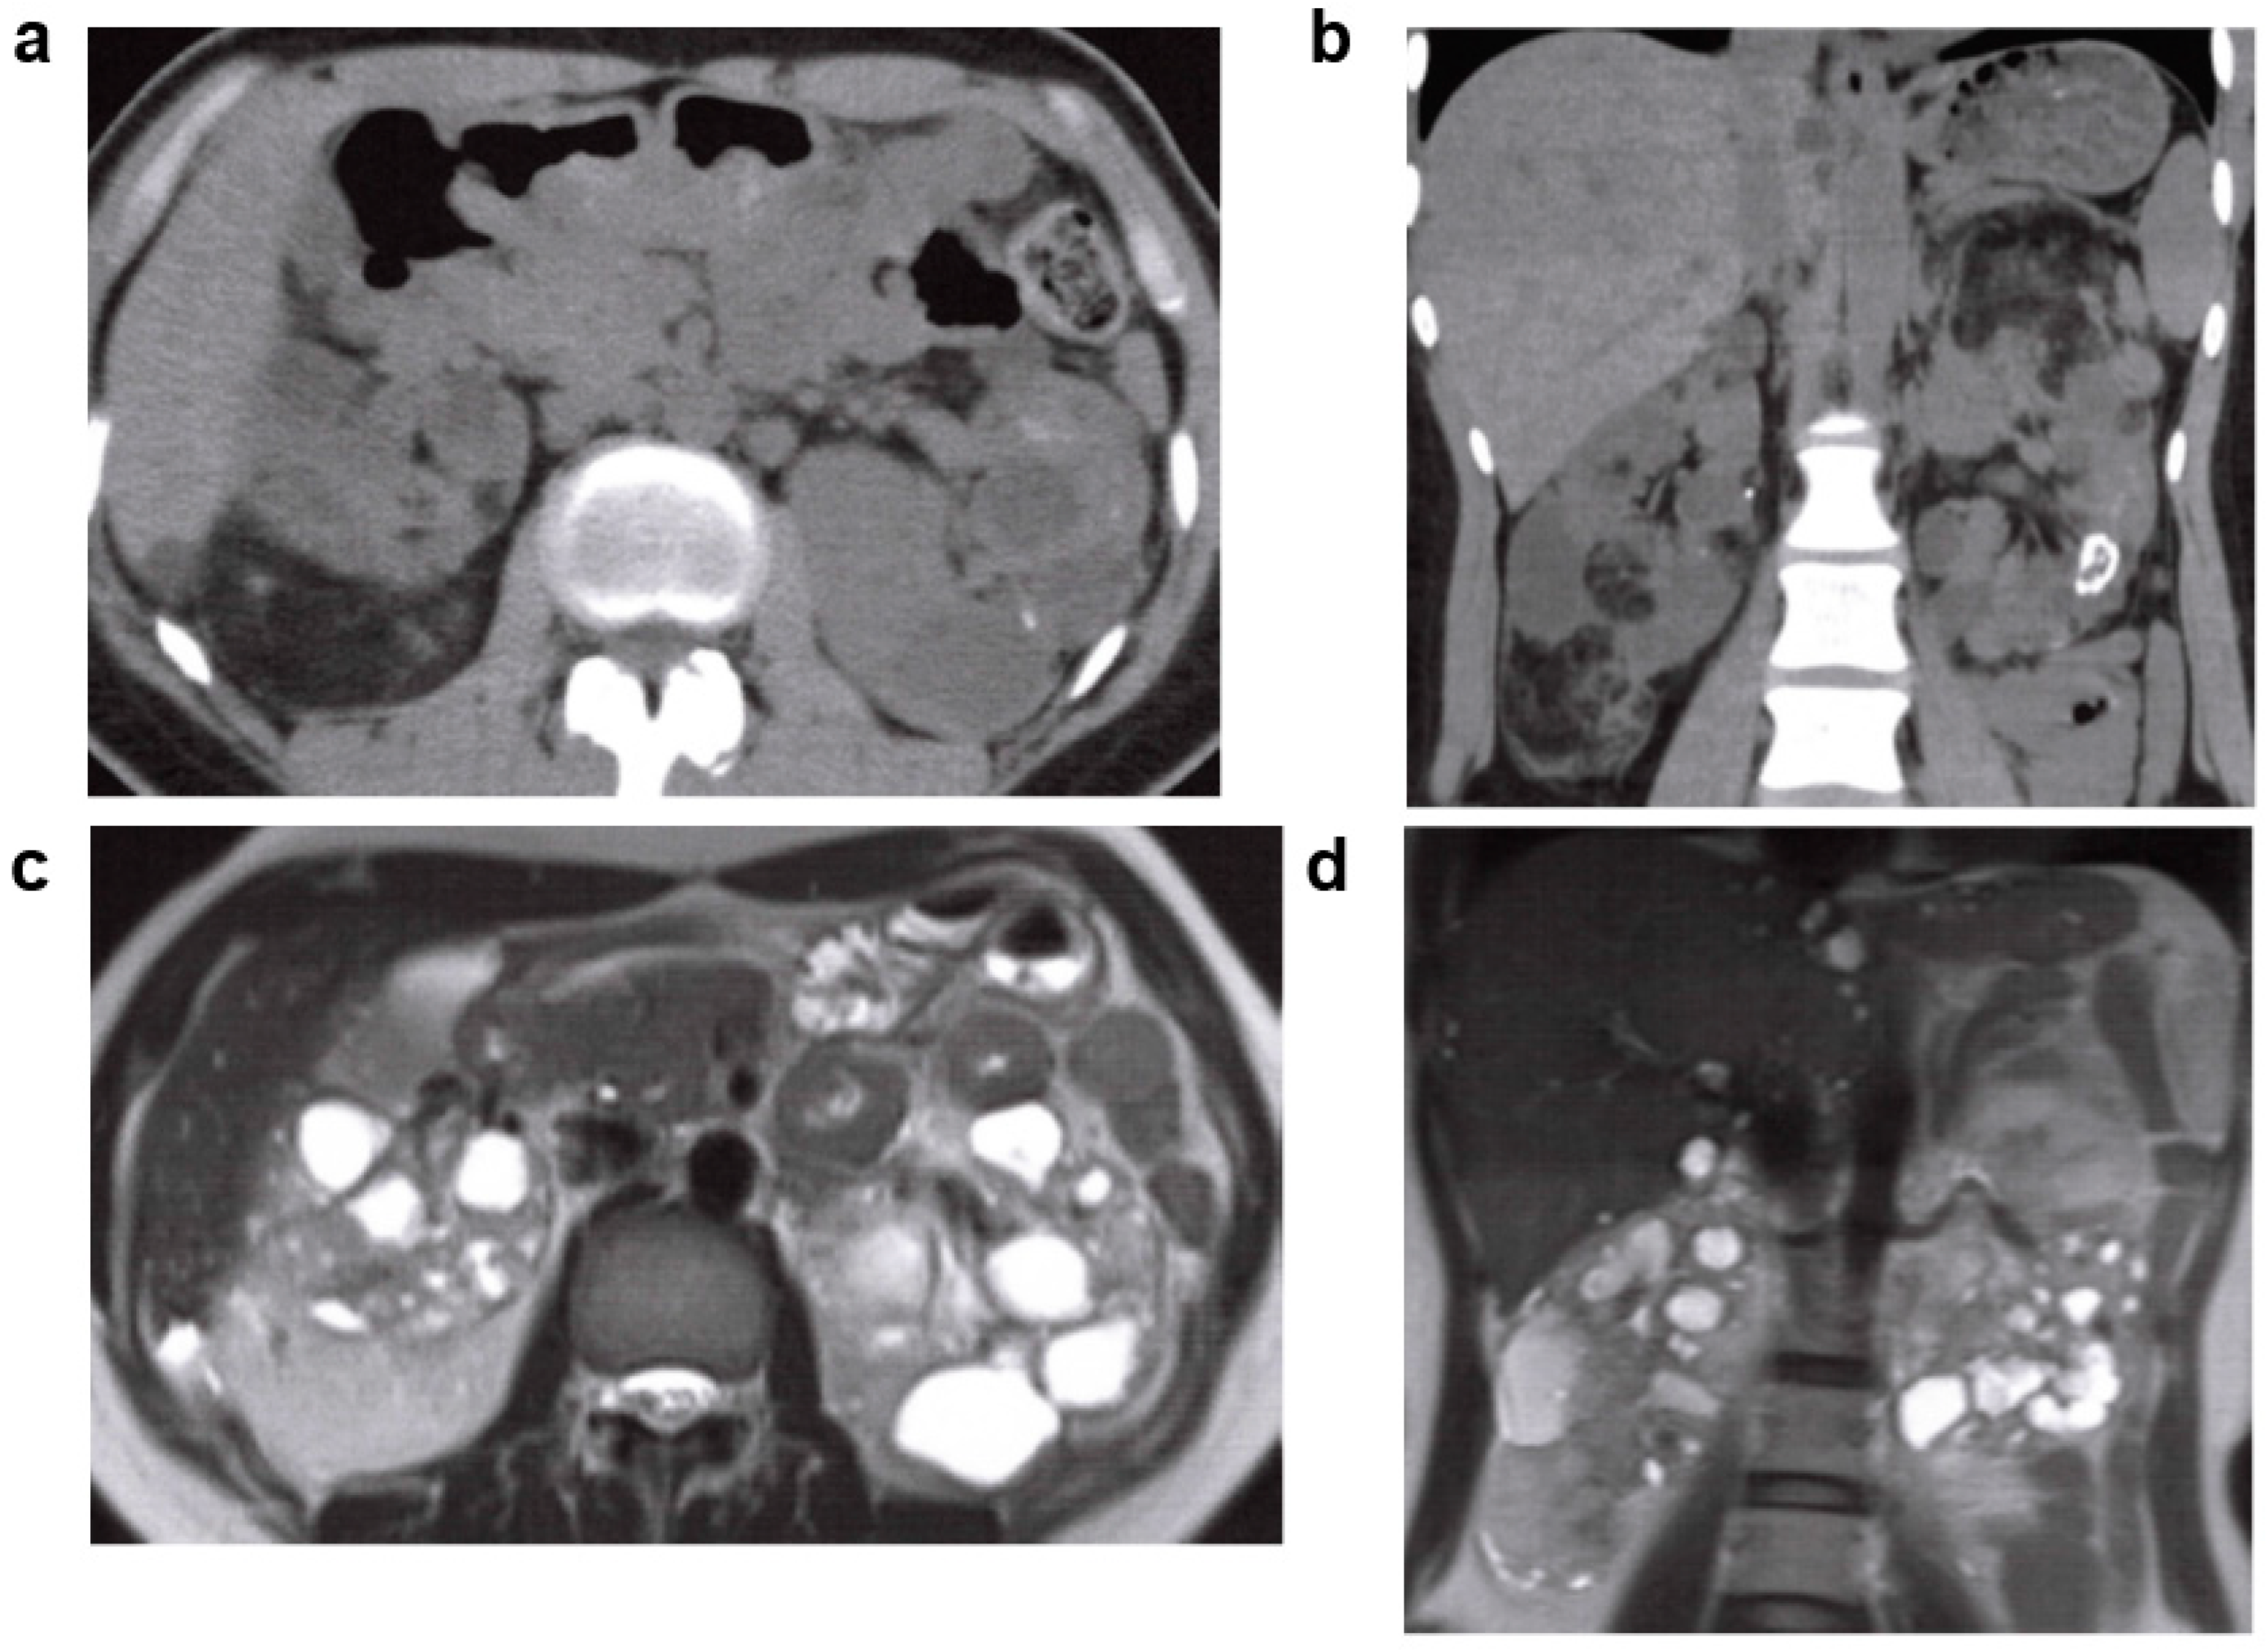

2.2. Acquired Cystic Kidney Disease (ACKD)